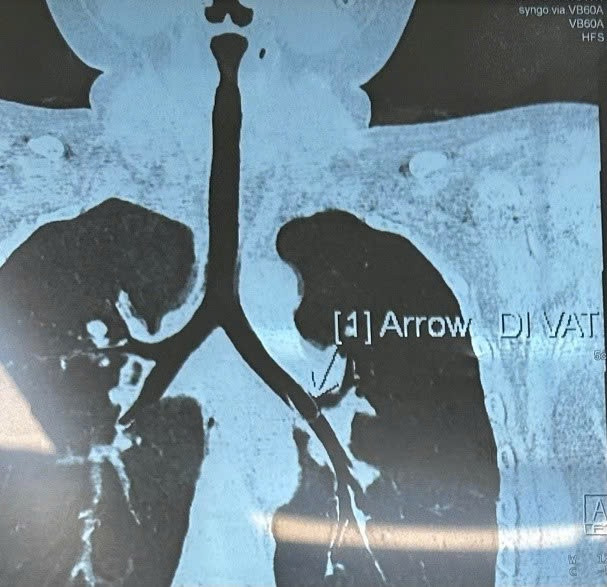

Sau 1 tuần khó thở không giảm, bé khám tại Bệnh viện Nhi Đồng 1, được chụp CT scan nghi ngờ có dị vật trong phế quản gốc trái.

| Hình ảnh CT Scan nghi ngờ có dị vật trong phế quản gốc trái. Ảnh BVCC |